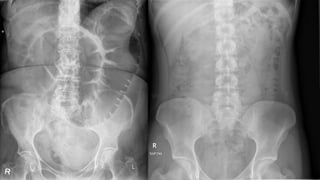

This document provides an overview of x-rays for medical students, covering topics such as ensuring x-rays are well-aligned, exposure levels, common artifacts and anatomical features, abdominal x-ray positions and views, and specialized x-rays including barium swallows, enemas, and tests to examine the esophagus, small bowel, biliary tree, and kidneys.